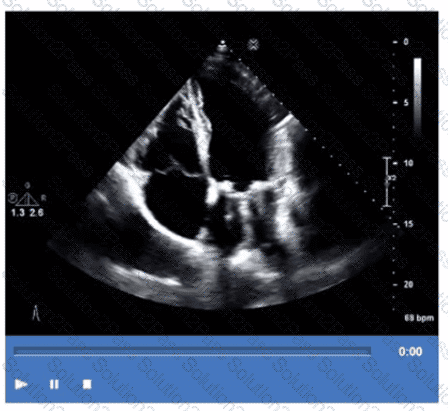

Which pathology is demonstrated in this video clip?